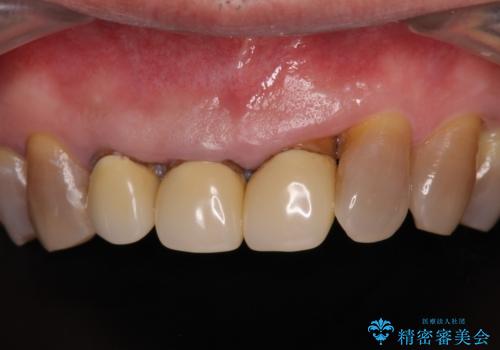

- 幼少期の薬剤の影響で歯が変色していていることを気にして来院された患者様です。

仕事も落ち着き、長年気にしていた前歯の色をきれいにしたいとのことでした。

上下ともに前歯のセラミッククラウンによる補綴治療を希望されていましたが、下顎前歯は叢生が強いため、補綴治療前に部分矯正を行って歯列を整えた上で、補綴治療を行うこととしました。